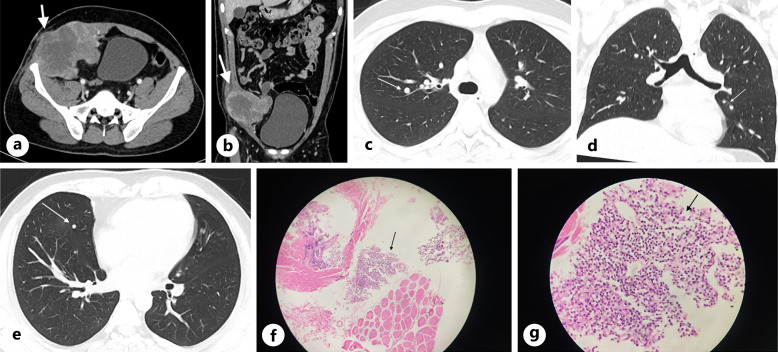

Case presentation: We report a case of a 27-year-old male presenting with right iliac fossa pain and a palpable mass, ultimately diagnosed as EES of the anterior abdominal wall. Radiological imaging revealed a soft tissue tumour within the rectus sheath with evidence of pulmonary metastasis. Histopathological analysis revealed small round blue cells, and immunohistochemistry demonstrated strong positivity for CD99, FLI1, WT1, and synaptophysin, confirming the diagnosis. Treatment was initiated with multi-agent chemotherapy and radiotherapy, and the patient remains under ongoing follow-up.